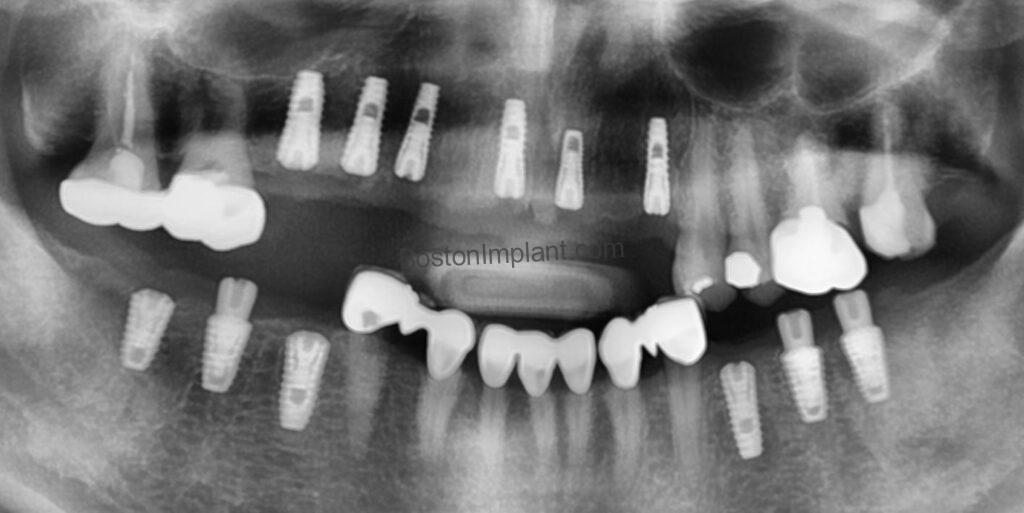

To ensure the highest precision and success, we utilized a surgical guide during the implant placement.

Surgical guides are invaluable in complex multiple implant cases. By allowing for meticulous pre-operative planning and virtual surgical simulations, we can optimize the implant placement strategy and develop the most effective treatment plan. Utilizing a surgical guide enabled us to successfully place all 12 implants in a single, efficient session. (For more information on surgical guides, please refer to my blog post about the ‘Surgical Guide for Dental Implant’.)

The next phase involved a three-month period of osseointegration, a vital process where the bone naturally bonds with the titanium implants. During this time, we addressed any minor issues, including root canal treatments and the creation of temporary crowns. We used this time effectively to ensure a solid foundation for her final restoration.